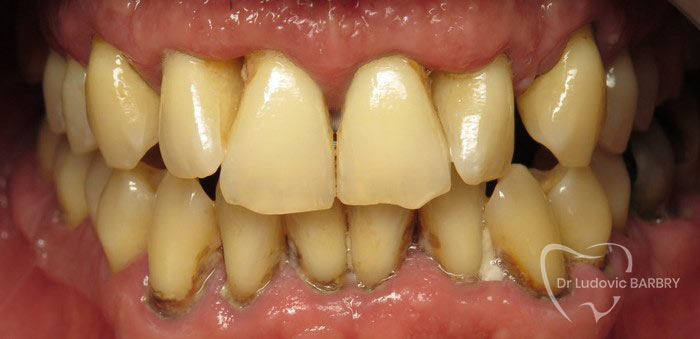

Parodontie Sévère

Grosse perte osseuse visible sur

la radio   on pourrait avec un stylet marquer en 2 couleurs le niveau osseux

actuel et normal

avant traitement

fin de traitement paro